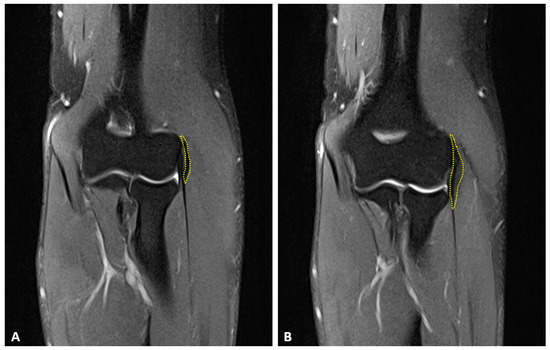

Background: Lumbar foraminal stenosis (LFS) is a prevalent degenerative condition associated with significant radicular pain and impaired quality of life. Advances in minimally invasive and fusion-based surgical techniques have introduced new strategies for decompressing the neural elements. However, comparative data correlating volumetric foraminal expansion with functional outcomes remain limited. Methods: This retrospective cohort study analyzed 256 patients treated surgically for symptomatic LFS between December 2017 and December 2023. Patients were categorized into four surgical subgroups: endoscopic decompression, anterior lumbar interbody fusion (ALIF), microsurgical decompression, and transforaminal lumbar interbody fusion (TLIF). Preoperative and postoperative assessments included magnetic resonance imaging (MRI) to calculate foraminal volume and standardized clinical scales: the Oswestry Disability Index (ODI), Visual Analogue Scale (VAS) for back and leg pain, and SF-36 health-related quality-of-life scores. Statistical significance was determined using p-values, and inter-observer agreement was evaluated via κ-statistics. Results: Postoperative imaging demonstrated a significant increase in foraminal canal volume across all surgical groups: endoscopy (29.9%), ALIF (71.8%), microsurgery (48.06%), and TLIF (67.0%). ODI scores improved from a preoperative mean of 55.25 to 18.27 at 24 months post-surgery (p < 0.001). VAS scores for back pain decreased from 6.37 to 2.1 (p < 0.001), while leg pain scores declined from 6.85 to 2.05 (p < 0.001). Functional improvement reached or exceeded the minimal clinically important difference (MCID) threshold in over 66% of patients. Conclusions: Modern surgical strategies for LFS, particularly fusion-based techniques, yield significant volumetric decompression and durable clinical improvement. Volumetric gain in the foraminal canal is closely associated with pain reduction and enhanced functional outcomes. These findings support a tailored surgical approach based on anatomical pathology and segmental stability.

Figure 1